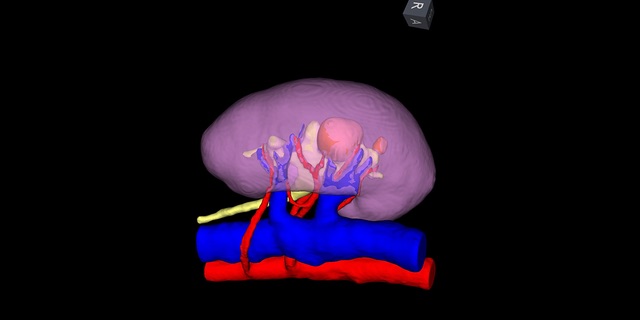

- Using your high-resolution images to create a 3D digital model of your kidney with IRIS™ -- for unparalleled surgery planning and guidance

We are the first of two centers in the U.S. to create a 3D digital model of your kidney for surgery planning and for navigation during tumor removal.

Our surgeons plan a roadmap for your surgery by visualizing the tumor in relation to surrounding structures in your kidney. Surgeons then use a real time image and align it with the intraoperative view for guidance from the robot’s console.

This technology has enabled some patients who would have had an entire kidney removed instead to have only the tumor removed while leaving remaining, functioning kidney tissue in place.